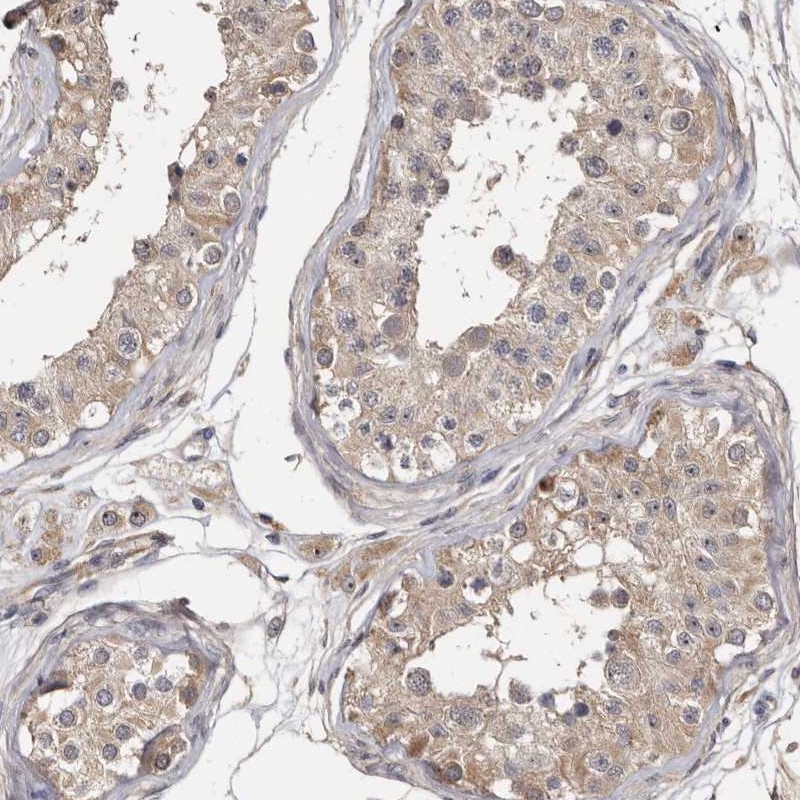

Immunohistochemical staining of human testis shows moderate cytoplasmic positivity in cells in seminiferous ducts and Leydig cells.